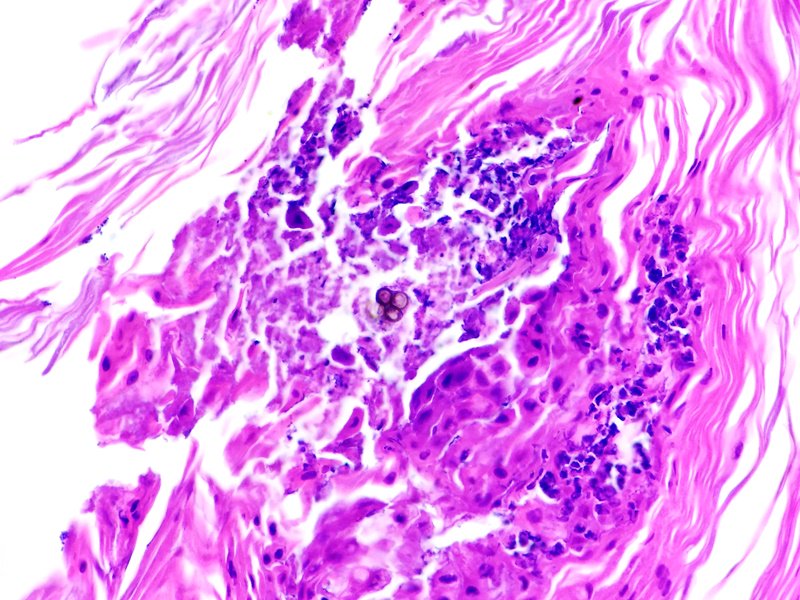

Cromoblastomicosis cutánea.